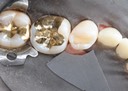

Kyle Chock #2 try in